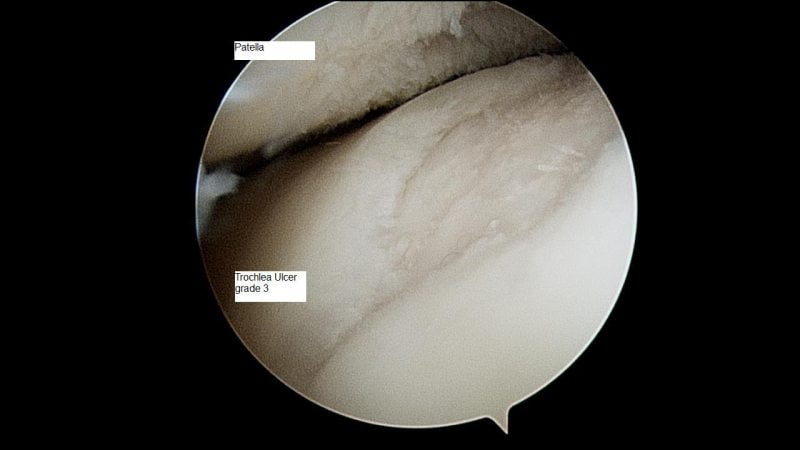

Начальная стадия артроза коварна еще и тем, что диагностировать ее сложно даже профессионалам и с применением аппаратных исследований. Рентгенография мало информативна: распознать заболевание по снимкам удается редко, только по уменьшению межсуставного зазора. Больше данных предоставляют артроскопия (введение инструмента для обследования в сочленение через микроразрез) и биохимический анализ взятой из сустава жидкости.

На начальном этапе дефартроз коварен тем, что сложно диагностируется аппаратными методами. Рентгенографическое исследование даст мало информации, патологический процесс распознается в редких случаях только по уменьшенному зазору между суставными поверхностями. Артроскопическое исследование с биохимическим анализом суставного ликвора дадут больше информации о патологическом процессе. Если у пациента боль иррадиирует в паховую или бедренную зону, то рекомендуется исключить патологии почек, репродуктивных органов и проконсультироваться у соответствующих специалистов.

- Рентгеновское исследование. На снимке можно увидеть незначительное утолщение хрящевой ткани и слабое сужение суставной щели. Одним из ранних признаков артроза суставов 1 степени являются остеофиты – костные наросты, формирующиеся вследствие патологических изменений хряща;